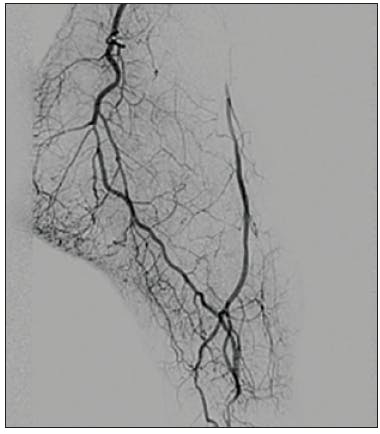

The initial angiogram confirmed an occlusion with extensive thrombus burden of a dominant left circumflex artery and TIMI 0 flow (Figure 1). Power aspiration with CAT RX and Penumbra ENGINE was started after wiring the dominant left circumflex artery. After one pass with CAT RX, the initial occlusion was removed. A second angiogram showed extensive clot burden spread across multiple branches (Figure 2). Each vessel was wired sequentially, delivering power aspiration via CAT RX to the site of each thrombus. A final angiogram revealed complete reperfusion to the dominant left circumflex artery and branches, with TIMI 3 flow (Figure 3).

We started with laser atherectomy followed by percutaneous transluminal angioplasty of the tibial peroneal trunk, peroneal artery, and posterior tibial artery. Angiography of the posterior tibial artery revealed embolization to the heel resulting in no flow to the foot (Figure 1). After one pass with mechanical thrombectomy using CAT RX, the thrombus was removed and flow was restored to the pedal arch via the plantar posterior tibial artery (Figure 2 and Figure 3).